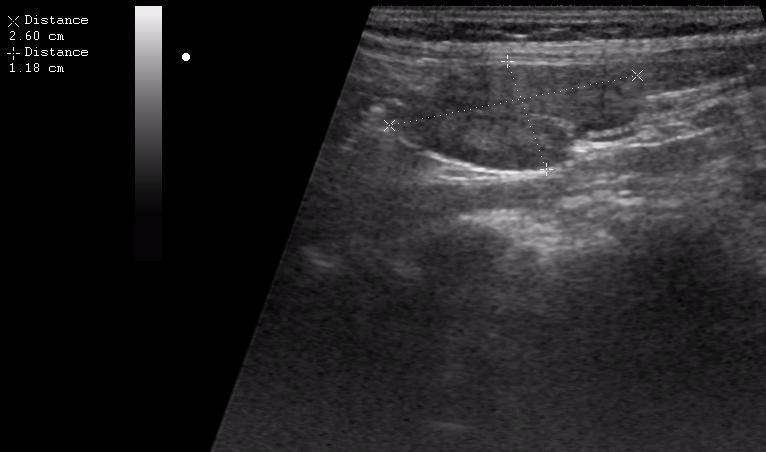

Мезентериальные лимфатические узлы: УЗИ и диагностика